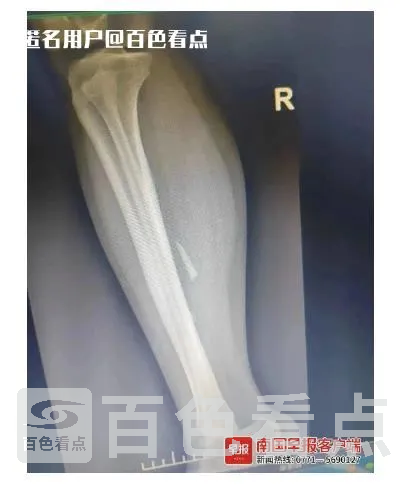

▲图为患者患处的影像资料。医院提供

据患者家属介绍,两年多前,小文右小腿曾被玻璃扎伤,但因伤口较小,家人未给予足够重视,并未让小文作拍片检查,只对伤口进行了简单处理。后来,小文小腿的伤口自行愈合了。

医师给小文作了相关检查后发现,她右小腿异物的位置与原有瘢痕位置有一定距离,考虑异物进入体内后随着肌肉收缩发生了位移。